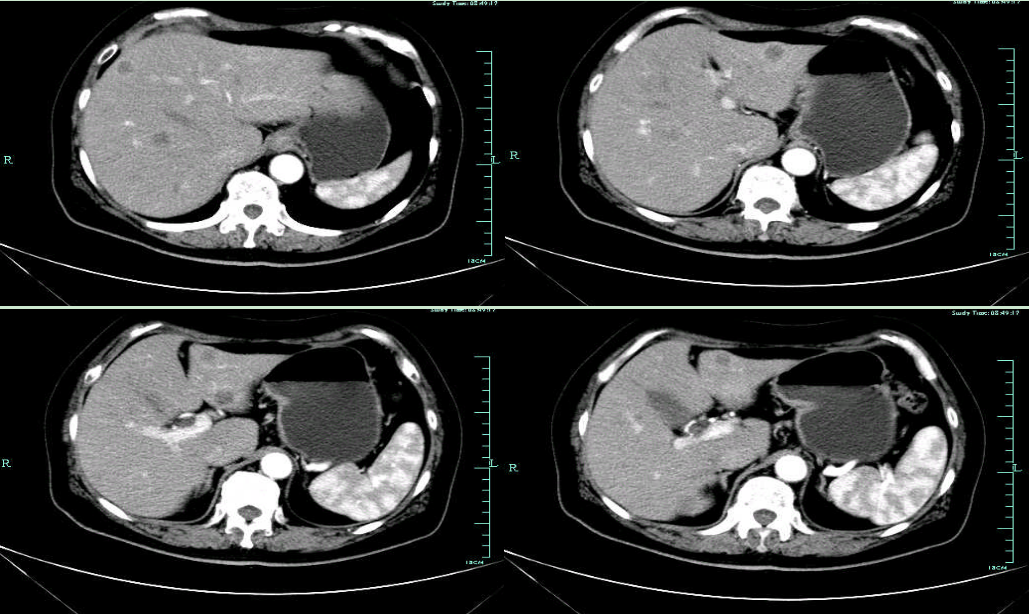

• CT示:肝转移

CT-T

CT-H1

影像学检查结果评估:cPD。